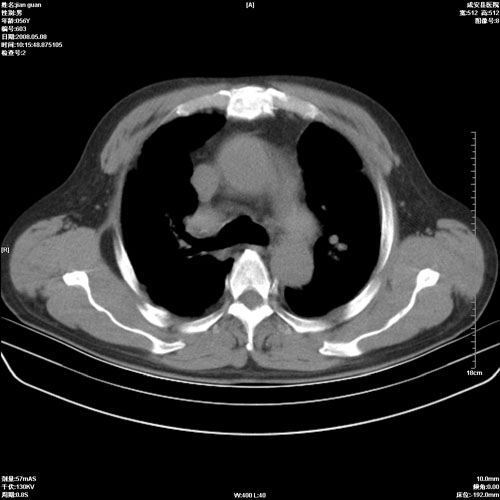

病人 男 60岁 主诉 胸闷 无明显发热 一般情况尚可。

考虑1心功不全,肺水肿

2右上肺结核纤维性病灶、肺气肿

2.心脏增大(以左心室增大为著),请结合b超及听诊.

2.肺门血管扩张,心脏增大,为肺心病

3.肺心病.

陈旧性肺结核,左心房扩大,左心衰竭

2右上肺结核纤维性病灶、肺气肿 ,肺心病